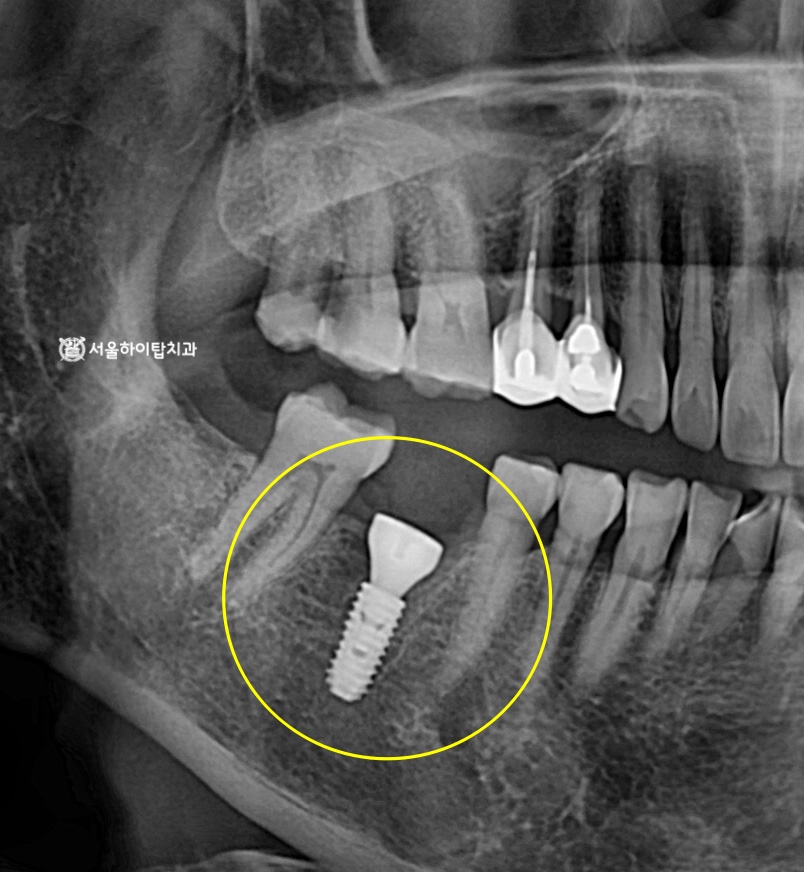

임플란트 식립 완료 – 골 유착

만수동 치과 에서는 앞선 가상 식립 시뮬레이션을 바탕으로

계획한 위치와 각도에 맞게 픽스처가 안정적으로 식립된 것을 확인할 수 있습니다.

주변 치조골과의 관계, 식립 깊이, 방향 모두

사전에 설정한 계획 범위 내에서 정확하게 이루어졌습니다.

이후 일정 기간 동안 픽스처와 주변 치조골이

단단하게 결합되는 골유착 과정을 충분히 거치게 됩니다.

최종 보철물 장착 – 지르코니아 크라운

종결 단계의 모습을 확인해 보면,

임플란트는 치조골 내에서 안정적인 지지를 받으며 단단히 고정되어 있습니다.

최종 보철물은 지르코니아 크라운으로 제작되어 강도와 내구성을 확보하였고,

기능적으로는 저작 시 안정적인 교합을 형성하며

심미적으로도 주변 치아와 자연스럽게 조화를 이루는 결과를 얻었습니다.